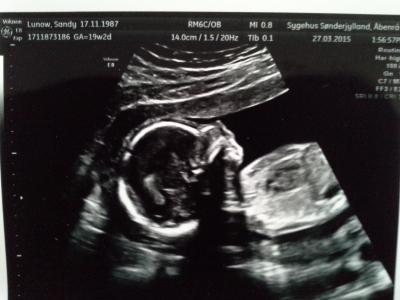

Von unsere kleinen Prinzessin. Total foto gen.

War ja vor 2 wochen heute ist hebame dran. Alles so wie es sei soll. Hat den normalen durchschnittliche Größe und gewicht zu den Zeitpunkt. Man konnte ihr kleines herzchen kmplet durchleuchten, die knochen im kanzen korper sehen und die durchblutung. Dan auch den magen wo sie etwas fruchtwasser drin jatte u d das anschein super sei. Ich persönlich find sie hat nen richtig susen Hintern, den hat sie uns mal gezeigt. Dazu noch starkearme und beine und diese kleine süße stups nase ein traum. Und sie ist sehr aktiv. Sie dreht sich oft ao das man meinen konnte sie sagt , schau mama ich bin auf den weg hier hin. Dan tretet sie auch oft. Ich bin total verliebt. ! Ein man kan sie nicht spüren aberer kann es sehen wen sie im bauch tretet oder sich dreht, natürlich wen ich liege.

das sind schöne Fotos, beneidenswert.. auf meinen erkennt man immer nix - die kann man drehen und wenden, man sieht alles drauf nur kein kind aber die schönsten werden wir dann alle im august spätestens september haben